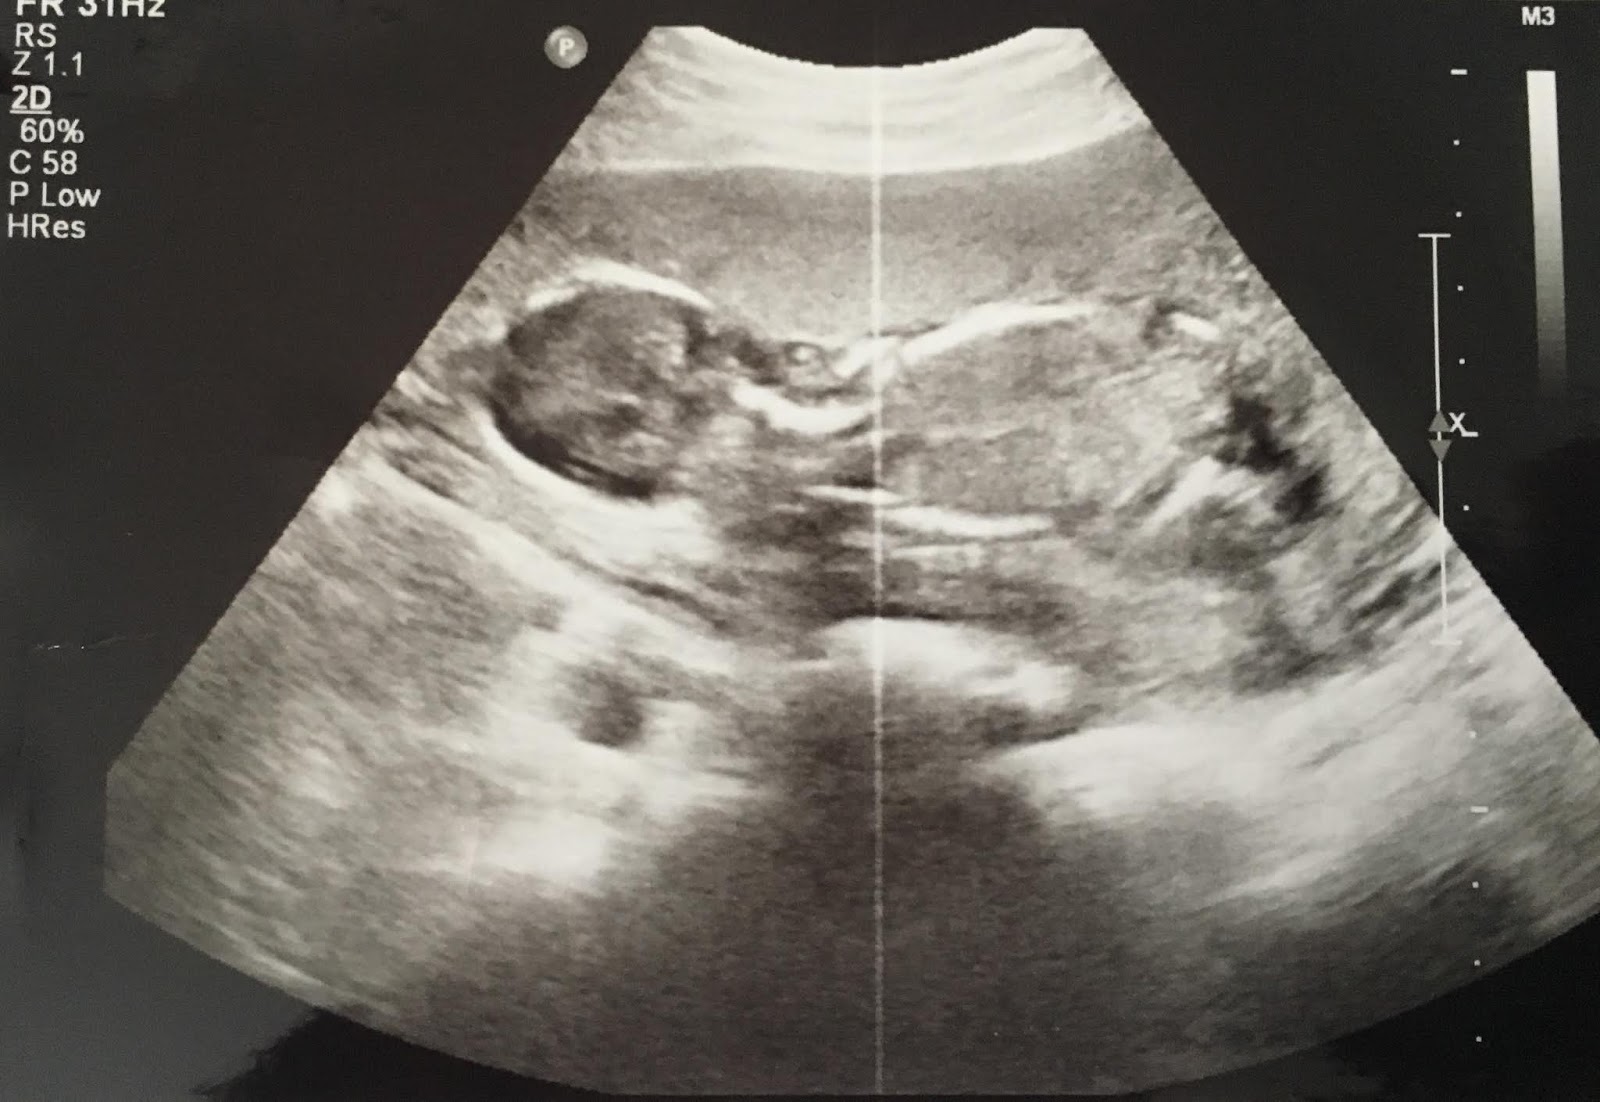

Throughout the Baby Chris project, we’ve been illustrating our articles with ultrasound images donated by Secular Pro-Life supporters. This week, we have two unusual photos to share. Mother Aimee explains:

I suffered from preterm premature rupture of membranes at 13 weeks and my pregnancy was deemed terminal for the duration of it. I received an ultrasound weekly until I delivered at 32 weeks so needless to say I have several ultrasound pictures to choose from. That being said, my fluid levels were very low (0-1.6cm) so they don’t look like a normal one. … I’ve been meaning to catalogue them anyway so I can show my daughter some day. This medically impossible child is currently rolling around in her crib refusing to nap.

![]() |

| 14 weeks 2 days, with rupture of membranes |